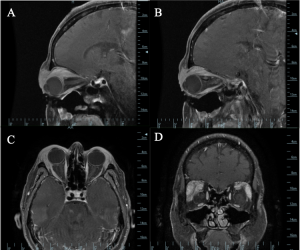

Imaging may be warranted for deeper xanthomas that present as an orbital mass, especially because the findings on CT and MRI are non-specific. Xanthomas may appear as well-circumscribed masses or as diffuse heterogenous enhancement surrounding orbital structures (Image 7).[4]

Bone xanthomas can have a varied appearance on imaging. On CT, the lesions may be well-defined, or they may have poorly defined borders. They often appear radiolucent with sclerotic margins and those in the craniofacial area tend to appear lytic.[3]

Xanthomas may present as orbital masses (Images 6 and 7) and the differential diagnosis can be extensive even after imaging, including inflammatory lesions, benign tumors and histiocytic disorders.

Bone xanthoma is rare and can appear similar to more common bone lesions on imaging, including benign fibrous histiocytoma, non-ossifying fibroma, simple bone cyst, fibrous dysplasia, giant cell tumor, or brown tumor of hyperparathyroidism.